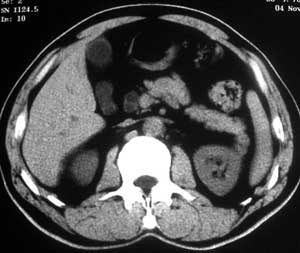

患者,男,57岁,梗阻性黄疸10余天。

这个病例胰头无明显增大,胆总管扩张明显而肝内胆管扩张更不明显,病程较短,

注意到十二指肠乳头明显突出,但尚光滑。分析以下可能性:

1、十二指肠乳头本身的病变,如乳头炎症;

2、急性乳头水肿,胆总管下端结石排石后乳头水肿;

3、壶腹部胆总管下端肿瘤累及十二指肠乳头。

十二指肠乳头粘膜慢性非特异性炎症